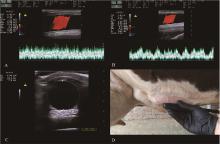

Fig. 5

Mammary vein frequency Doppler examination of cows[75] A. Blood flow characteristics of the mammary veins of cows on day 14 of lactation; B. Blood flow characteristics of the mammary veins of cows on day 35 of dry milking; C. Distance, diameter, and cross-sectional area of the mammary veins from the surface of the skin; D. Mammary localization position of the Doppler imaging probe"